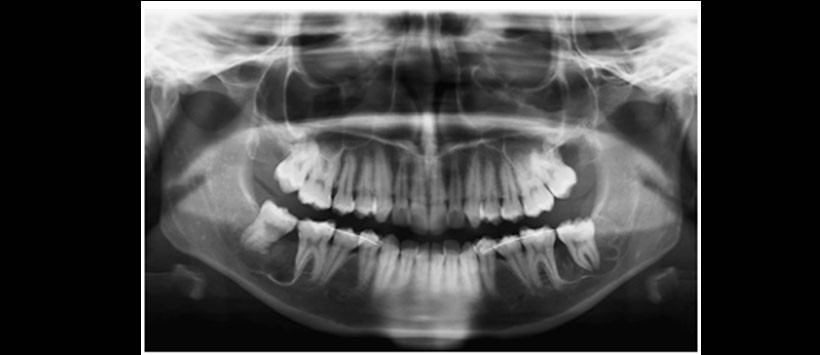

Se presenta un caso en el cual se realiza el autotransplante de los terceros molares mandibulares como medio alternativo de sustitución de los segundos molares que requieren extracción por su retención. La radiografía panorámica muestra las piezas 3.7 y 4.7 impactadas en posición horizontal y las piezas 3.8 y 4.8 en posición mesioangular. Se eligieron a las piezas 3.8 y 4.8 como piezas donantes de las piezas 3.7 y 4.7 respectivamente. Posterior al autotransplante (1mes post operatorio) se realizó el tratamiento de conductos de las piezas donantes y se realizaron controles radiográficos hasta un año posoperatorio.

Figura 1: Radiografía panorámica preoperatoria que muestra las piezas 1.8, 2.8, 3.8, 3.7, 4.7 y 4.8 impactadas. De las cuales las piezas 3.7 y 4.7 se encuentras impactadas en una posición horizontal casi completamente intraóseas.